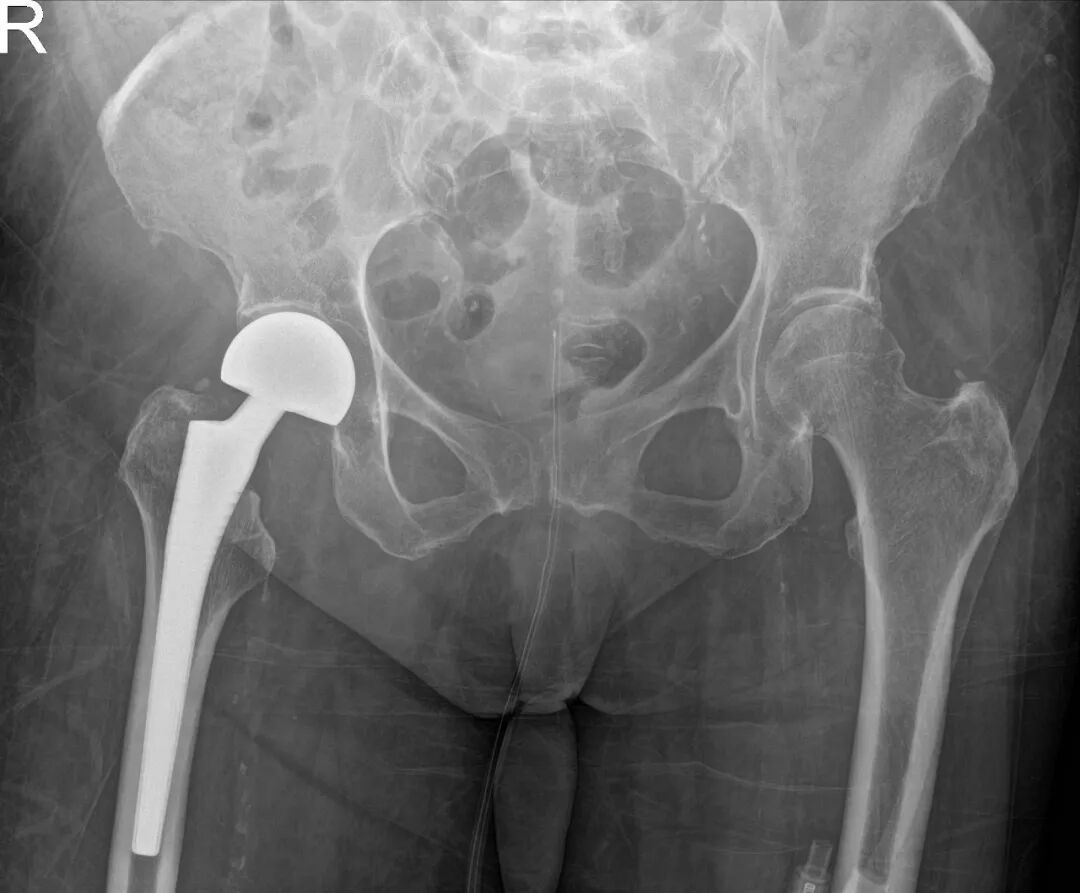

手术当日,在麻醉科执行主任刘建慧和手术室护士长姚英的支持下,麻醉团队、器械护士与巡回护士紧密配合,为手术保驾护航。王家骐亲自主刀,带领运动医学科手术团队,凭借丰富的临床经验与娴熟的手术技巧,为谢阿姨成功实施人工股骨头置换术。术中,团队操作精准、配合默契,从切开到假体安装一气呵成,最大限度缩短手术时间,减少手术创伤,为术后快速康复奠定基础。

患者术后恢复顺利,伤口愈合良好。肾脏内科持续跟进和优化透析方案,保持患者肾功能稳定。经过康复医学科介入下的系统康复训练,患者逐渐恢复行走能力。出院那天,患者及家属万分感激。